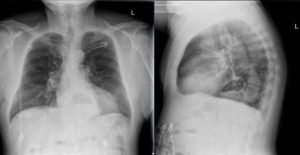

The two-view chest X-ray shows mild opacification of the bilateral lower lobes concerning for pneumonia (red arrows). Incidental retrocardiac opacity with air-fluid level consistent with large hiatal hernia is also observed (green arrow).

In this case, the chest X-ray was concerning for pneumonia, and a large, incidental hiatal hernia was also appreciated. Patient was started on antibiotics for the pneumonia and admitted to internal medicine. The hiatal hernia was not operated on because the patient was asymptomatic.